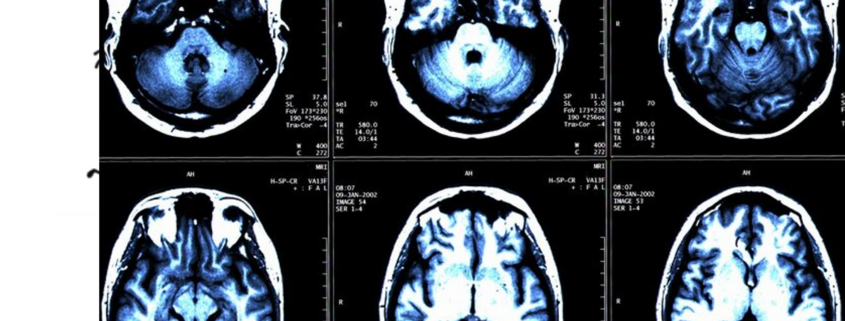

Hirn-Scan deckt Legasthenie bei Kindern auf – Was bringt das?

Forscher am Max-Planck-Institut sollen herausgefunden haben, dass eine MRT-Aufnahme des Gehirns im Vorschulalter zeigen kann, ob ein Kind an einer Lese-Rechtschreibschwäche leidet. Damit soll Frühförderung möglich werden. Aber die könnte es auch so geben, wenn die Verantwortlichen wollen würden. …